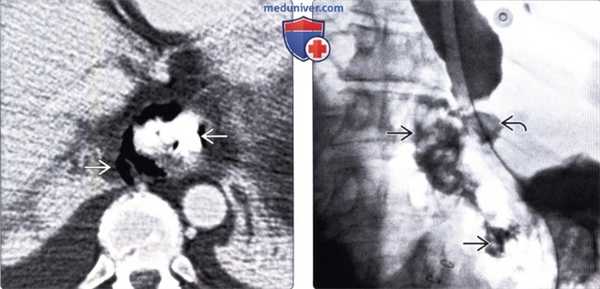

(Справа) На рентгенограмме пищевода, полученной при рентгеноскопии после введения водорастворимого контрастного вещества через назогастральный зонд, определяется утечка контраста SB через поврежденный участок в области левой передней стенки дистального отдела пищевода - типичные изменения при синдроме Бурхаве. (Слева) На аксиальной КТ с контрастным усилением, выполненной мужчине среднего возраста, предъявляющего жалобы на сильную боль в груди, появившуюся после повторной рвоты, визуализируется газ и контраст вне просвета пищевода, в окопопищеводных тканях и в нижнем средостении, верхних отделах брюшной полости.

(Справа) На рентгенограмме пищевода с водорастворимым контрастным веществом, введенном по назогастральному зонду, выполненной во время рентгеноскопии этому же пациенту, визуализируется контраст в средостении и в верхних отделах брюшной полости. Разрыв произошел в области левой передней стенки пищевода в дистальных отделах.

(Слева) На аксиальной КТ с контрастным усилением, выполненной мужчине среднего возраста, предъявляющего жалобы на сильную боль в груди, появившуюся после повторной рвоты, визуализируется газ и контраст вне просвета пищевода, в окопопищеводных тканях и в нижнем средостении, верхних отделах брюшной полости.